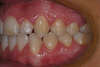

Béance traitée par gouttières

Début du traitement

Fin du traitement